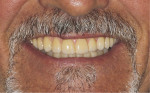

Three weeks later, the laboratory returned a screw-retained, acrylic full-arch interim hybrid prosthesis (Figure 4 and Figure 5). The healing abutments were removed, the provisional prosthesis was inserted, and the fixation screws were tightened. After seeing the prosthesis in his mouth, the patient indicated that he was happy with the esthetics. Radiographs were taken to verify the fit and mating of the interim hybrid prosthesis (Figure 6).

The patient wore the maxillary interim hybrid prosthesis for a period of 3 weeks to confirm the occlusion and verify that the esthetics met his expectations.

The provisional acrylic hybrid prosthesis was removed from the mouth and compared extraorally with the monolithic zirconia hybrid prosthesis, which demonstrated identical tooth positions and esthetics that had been approved by the patient (Figure 8). When the acrylic screw-retained hybrid prosthesis was removed, the underlying soft tissue demonstrated a healthy noninflamed gingival cuff at each implant site. For the screw access channel of the right canine-premolar implant to be placed in a nonesthetic location, a multi-unit abutment was required to correct the emergence angle (Figure 9). This multi-unit abutment had been placed when the acrylic hybrid prosthesis was initially inserted. The zirconia full-arch hybrid prosthesis was seated on the maxillary arch, and the fixation screws were torqued to the manufacturer's recommended value (Figure 10). Once seated, periapical radiographs were taken to verify that the prosthetics properly mated with the implants without any misfit at the connectors (Figure 11). The screw access channels in the zirconia monolithic full-arch hybrid prosthesis were then filled with polytetrafluoroethylene (PTFE) (ie, plumber's) tape to block the screw heads and then restored with composite (Filtek™, 3M) to seal the access openings (Figure 12). The occlusion was checked, and no adjustments were required. At the completion of the case, the resulting stable prosthesis met the patient's initially expressed goals, providing esthetics and a return to function (Figure 13 and Figure 14).